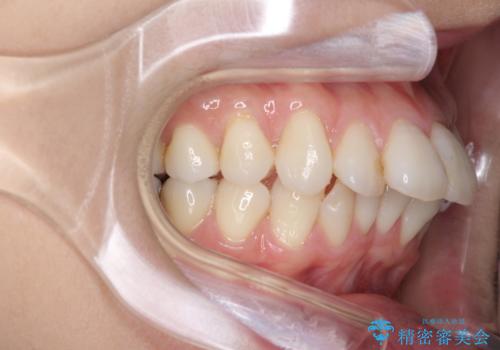

インビザラインでの前歯のガタガタの矯正

- 上下の前歯のがたつきを主訴に来院されました。

歯と歯の間をわずかに削りスペースを作り、インビザラインにて矯正治療を行うこととしました。

使用時間を守っていただけたので、スムーズに矯正を終了することができました。